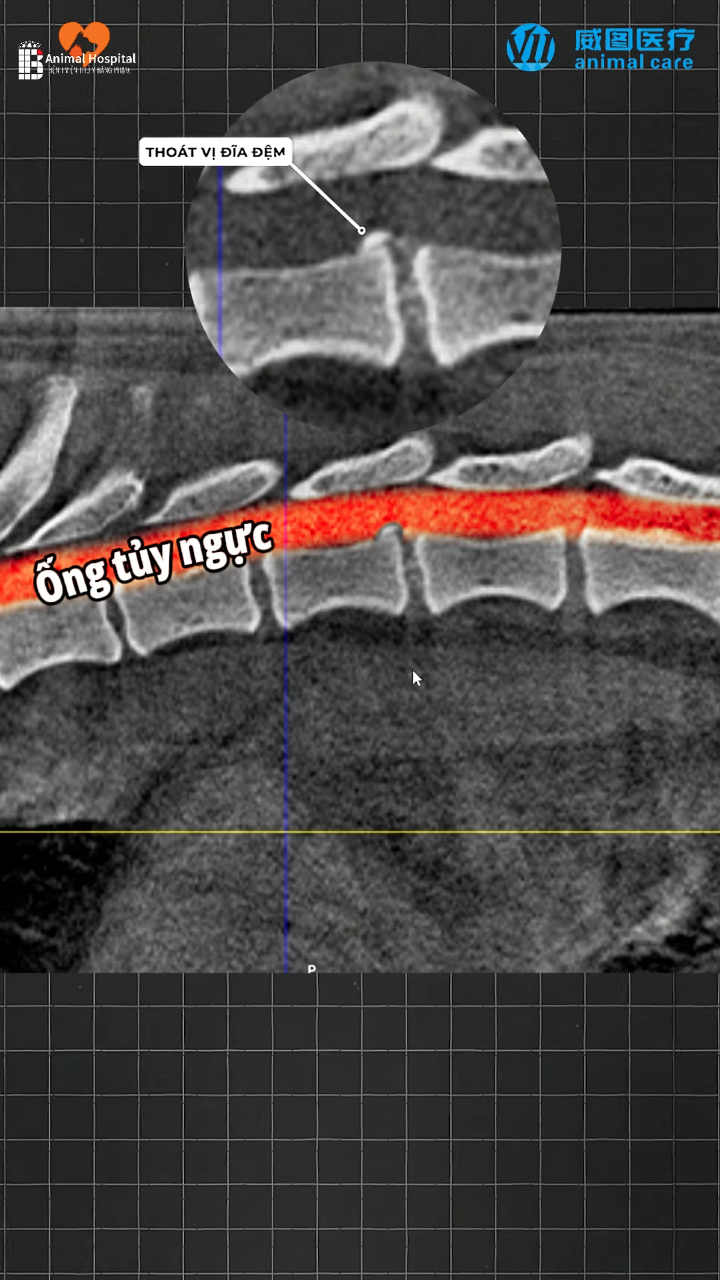

Dịch vụ phẫu thuật cố định cột sống và thoát vị đĩa đệm ở chó mèo – Chẩn đoán và điều trị bệnh lý đĩa đệm C3 – C4 ở bạn chó Bomi

Báo cáo ca lâm sàng: Thoát vị đĩa đệm C3 - C4 ở chó Bomi